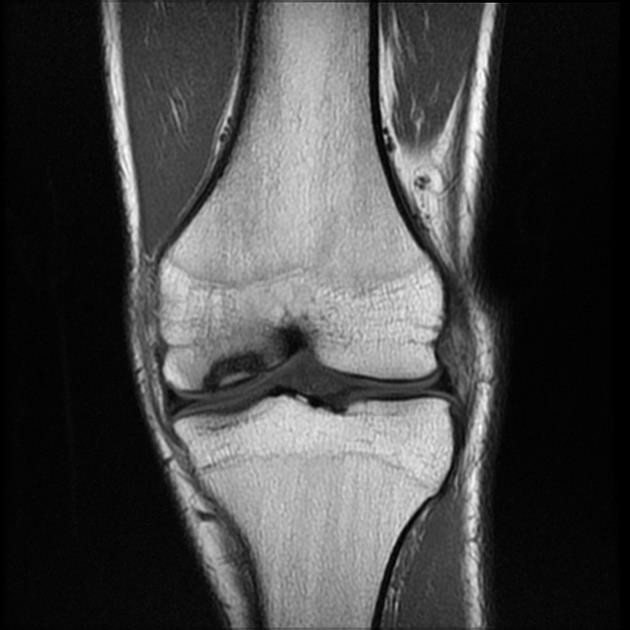

Специфическим признаком РВС является остеохондрит Вегенера - поражение длинных трубчатых костей на границе эпифиза и диафиза, обусловленное нарушением образования кальция и торможением развития остеобластов. Выделяют три степени остеохондрита. Характерными для РВС являются II и III степени. Наряду с остеохондритом, у детей грудного возраста часто обнаруживаются периостальные наложения при рождении и в первые месяцы жизни, поражающие длинные трубчатые кости и череп. Остеохондриты и периоститы обнаруживаются симметрично в нескольких костях. Возможно развитие гумм в метафизах и диафизах, вызывающих переломы и псевдопаралич Парро. При этом наблюдается локальная болезненность и отек в зоне поражения. Конечность выглядит парализованной, но чувствительность и движения пальцев сохранены. Возможно развитие фалангитов или дактилитов с деструктивными гуммозными и периостальными изменениями [1, 5, 29]. Данные поражения протекают безболезненно и не образуют свищей. По нашим данным, самым частым признаком РВС на сегодня является поражение костей. У 43 (56,6%) больных был диагностирован остеохондрит II степени, а у 3 (3,9%) - III (рис. 4, а, б). Рисунок 4. (а, б). Остеохондрит II степени у новорожденного с РВС. Часто выявлялись периоститы трубчатых костей, сочетающиеся с остеохондритами II степени (рис. 5, а, б). Рисунок 5. Сифилитический диффузный остиомиелит трубчатых костей (внутриметадиафизарный перелом проксимального отдела плечевой кости) до проведения специфической терапии (а) и после лечения (б). Псевдопаралич Парро наблюдался у 1 ребенка (рис. 6). Рисунок 6. Псевдопаралич Парро левой руки у ребенка 1,5 мес с РВС. Также у 1 ребенка, поступившего в возрасте 2,5 мес, диагностирован остеохондрит II степени, периостит, эпифизарная гумма фаланги II пальца кисти и фалангит, возникающий то на одном, то на другом пальце.